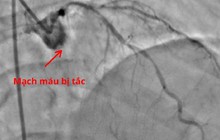

Tử cung lạnh chỉ tình trạng năng lượng dương không thể làm ấm cơ thể, nhất là tử cung. Điều này khiến mạch máu tử cung co thắt lại, khiến tử cung thiếu máu nuôi, niêm mạc tử cung thiếu độ ẩm, lớp lót tử cung không đáp ứng thích hợp với hormone dương hay progesterone. Từ đó những hoạt động ở tử cung khó có thể diễn ra thuận lợi, gây khó rụng trứng và thụ thai thành công. Dần dần diễn tiến đến hiếm muộn, thậm chí là vô sinh ở nữ giới.